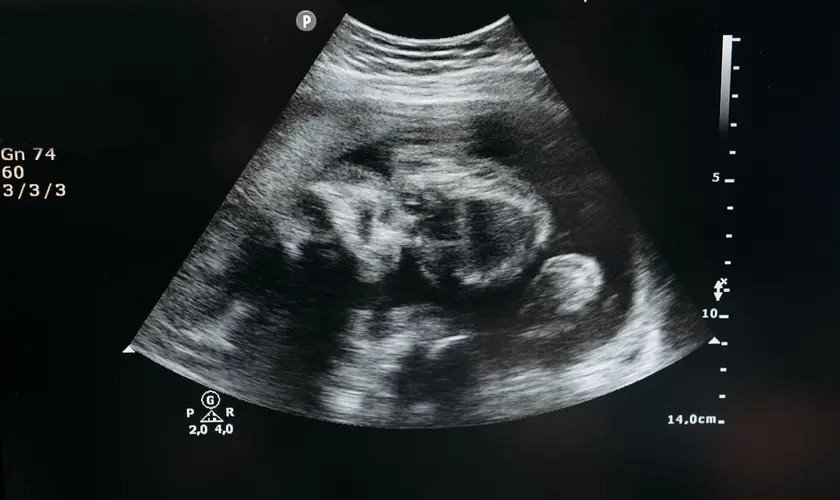

Em dezembro passado, Jenniffer González-Colón, governadora de Porto Rico, aprovou a Lei 183-2025, que altera o Código Civil porto-riquenho e reconhece o nascituro — um termo jurídico em latim que se refere a “concebido, mas não nascido” — como pessoa natural desde a concepção.